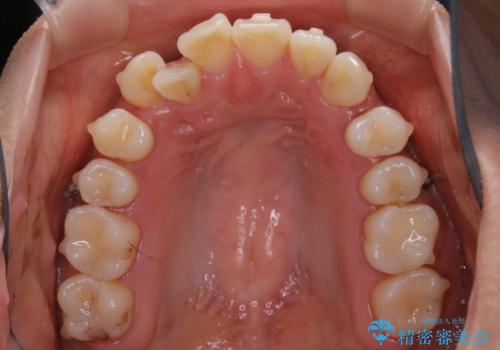

【非抜歯】インビザライン 隠れた前歯を並べる矯正治療

- 前歯のガタつき・奥に隠れてしまっている歯の矯正治療を希望されて初診来院されました。

顔貌的に口元を下げたいといった希望はなく抜歯はなるべく避けたいとのご要望からマウスピース装置(インビザライン)での治療を行うこととなりました。